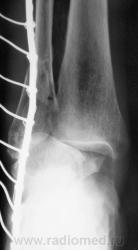

Перелом наружной и задней лодыжек. Подвывих в голеностопном суставе кнутри. Подвывих в тараннопяточном суставе. Разрыв дистального межберцового сочленения.

Переломы латеральной и медиальной лодыжек, пронационный подвывих в голеностопном суставе, латеральный подвывих в таранно-пяточном, разрыв межберцового синдесмоза.

Almo правильно задал вопрос, это касается терминологии. Про вывих стопы говорят, когда имеется вывих в г/ст суставе, а подтаранный N. Если имеется вывих в голенностопе и в подтаранном в противоположные стороны, т.е. смещается только таранная кость, говорят о вывихе таранной кости. Данный случай относится именно к последнему.